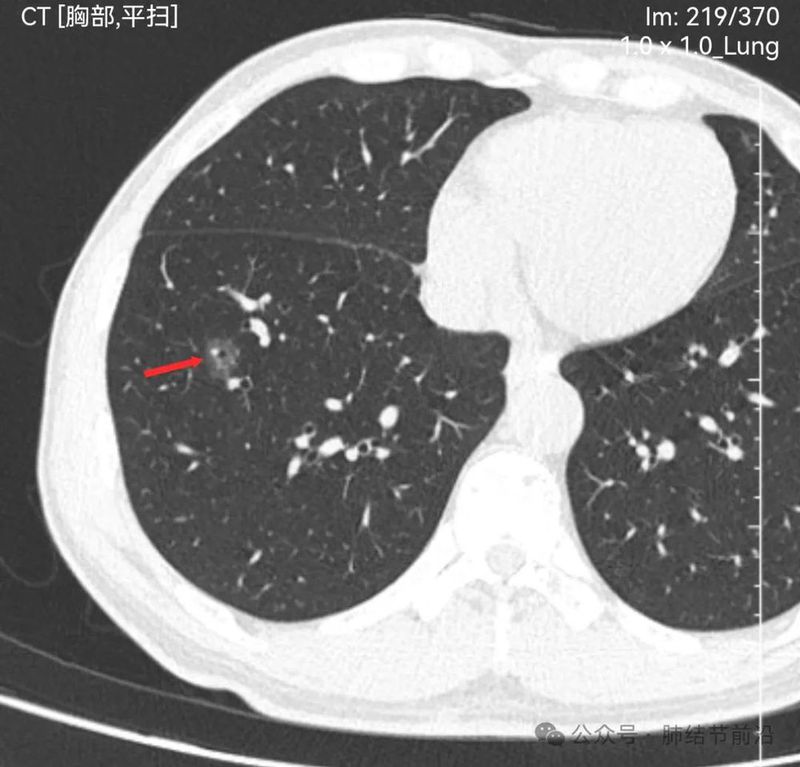

见右下肺纯磨玻璃结节14mm。有“血管穿过”、空泡。磨玻璃边界清楚而不毛糙。形态上是典型的肿瘤性磨玻璃,以微浸润腺癌可能大。